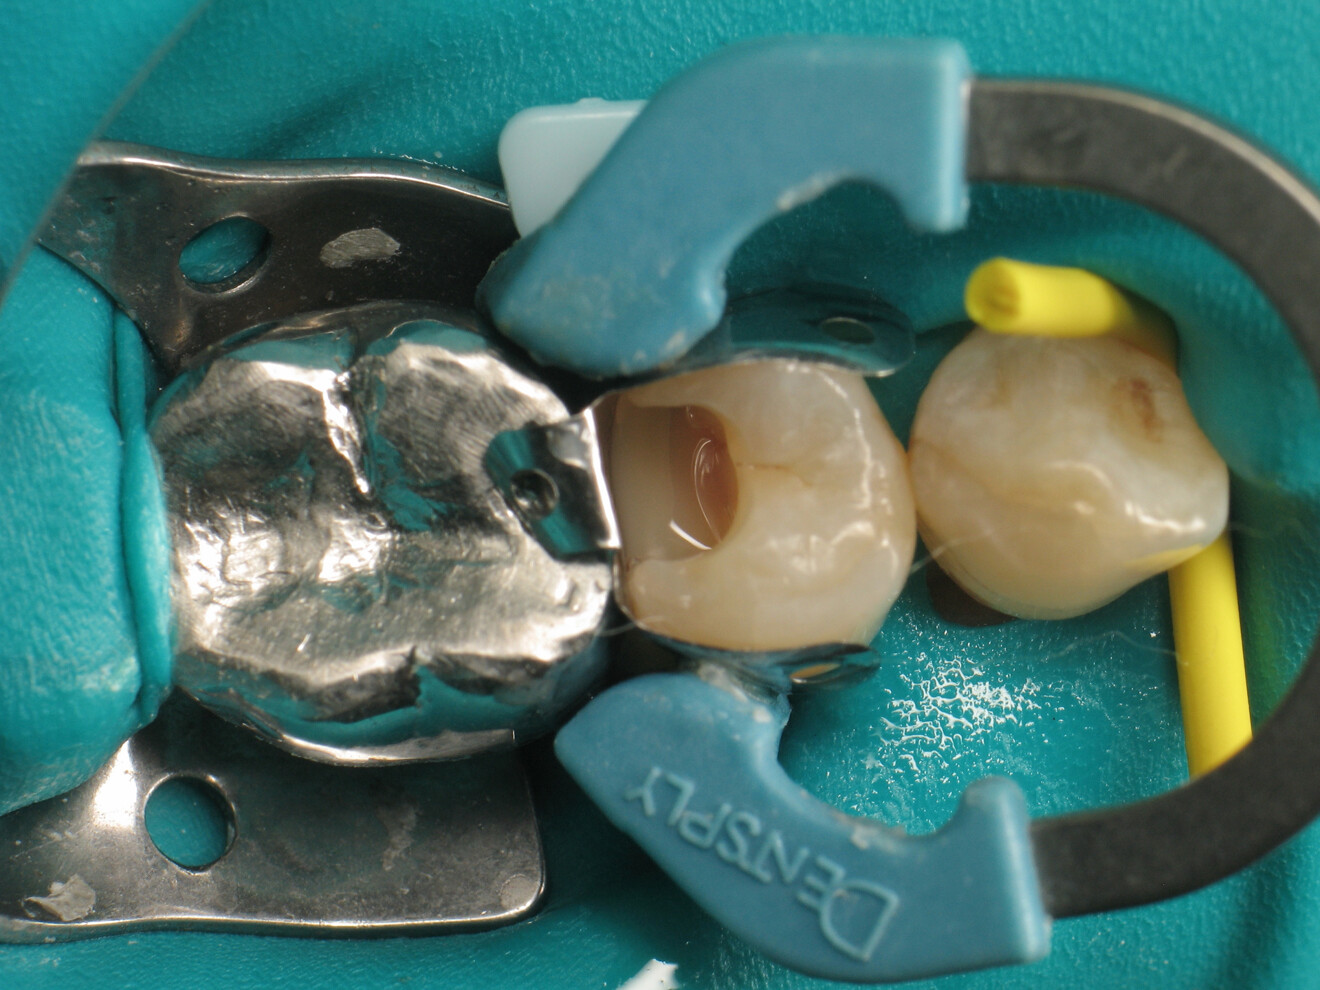

Fig. 4: Placement of the proximal matrix.